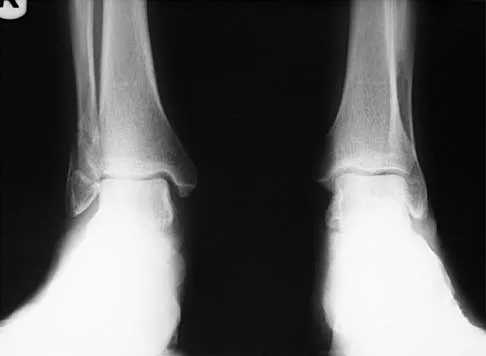

A 57-year-old man has had right ankle pain for the past 10 months following an injury that went untreated. Radiographs are shown in Figures 30a through 30c. Management should consist of